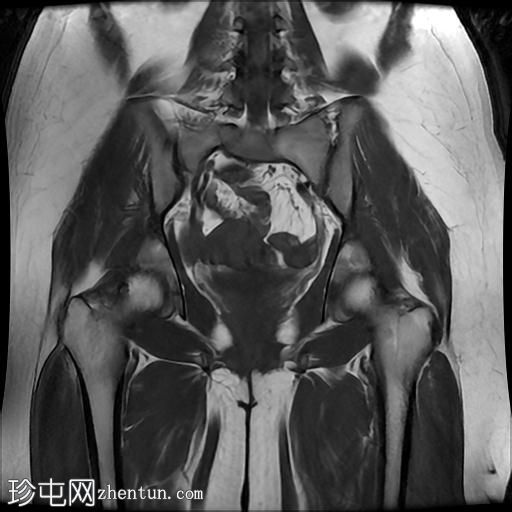

MRI

轴位

T2加权像

T1加权像

冠状位

臀中肌髂骨起点处前侧全层撕裂,伴有充满液体的间隙,以及髂骨髓水肿。

MRI结果符合臀中肌近端髂骨起点处全层撕裂的

影像

学表现。